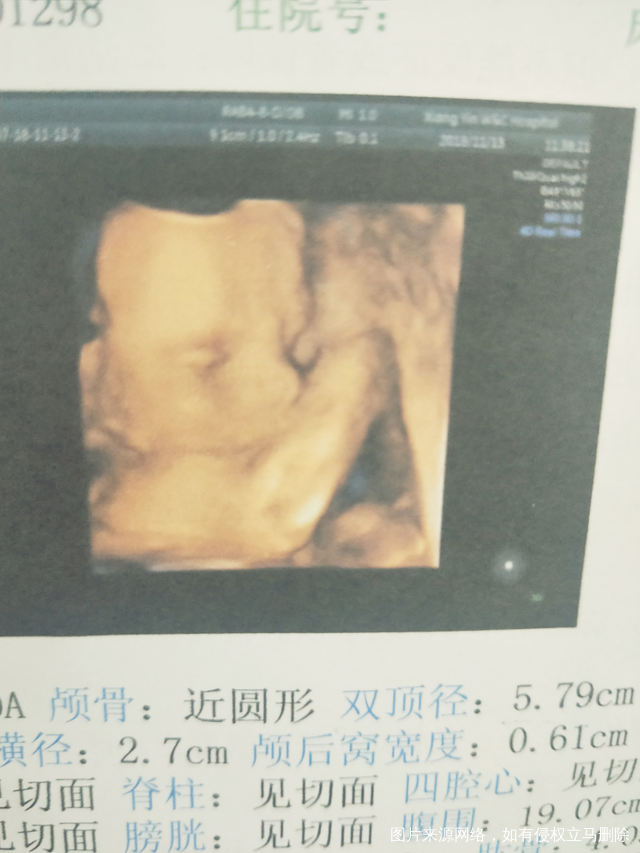

今日做了四维一切都正常!好好奇是男孩还是女孩!

哈哈,时间过的太快,就5个半月了,期待我们宝宝来到我们家!